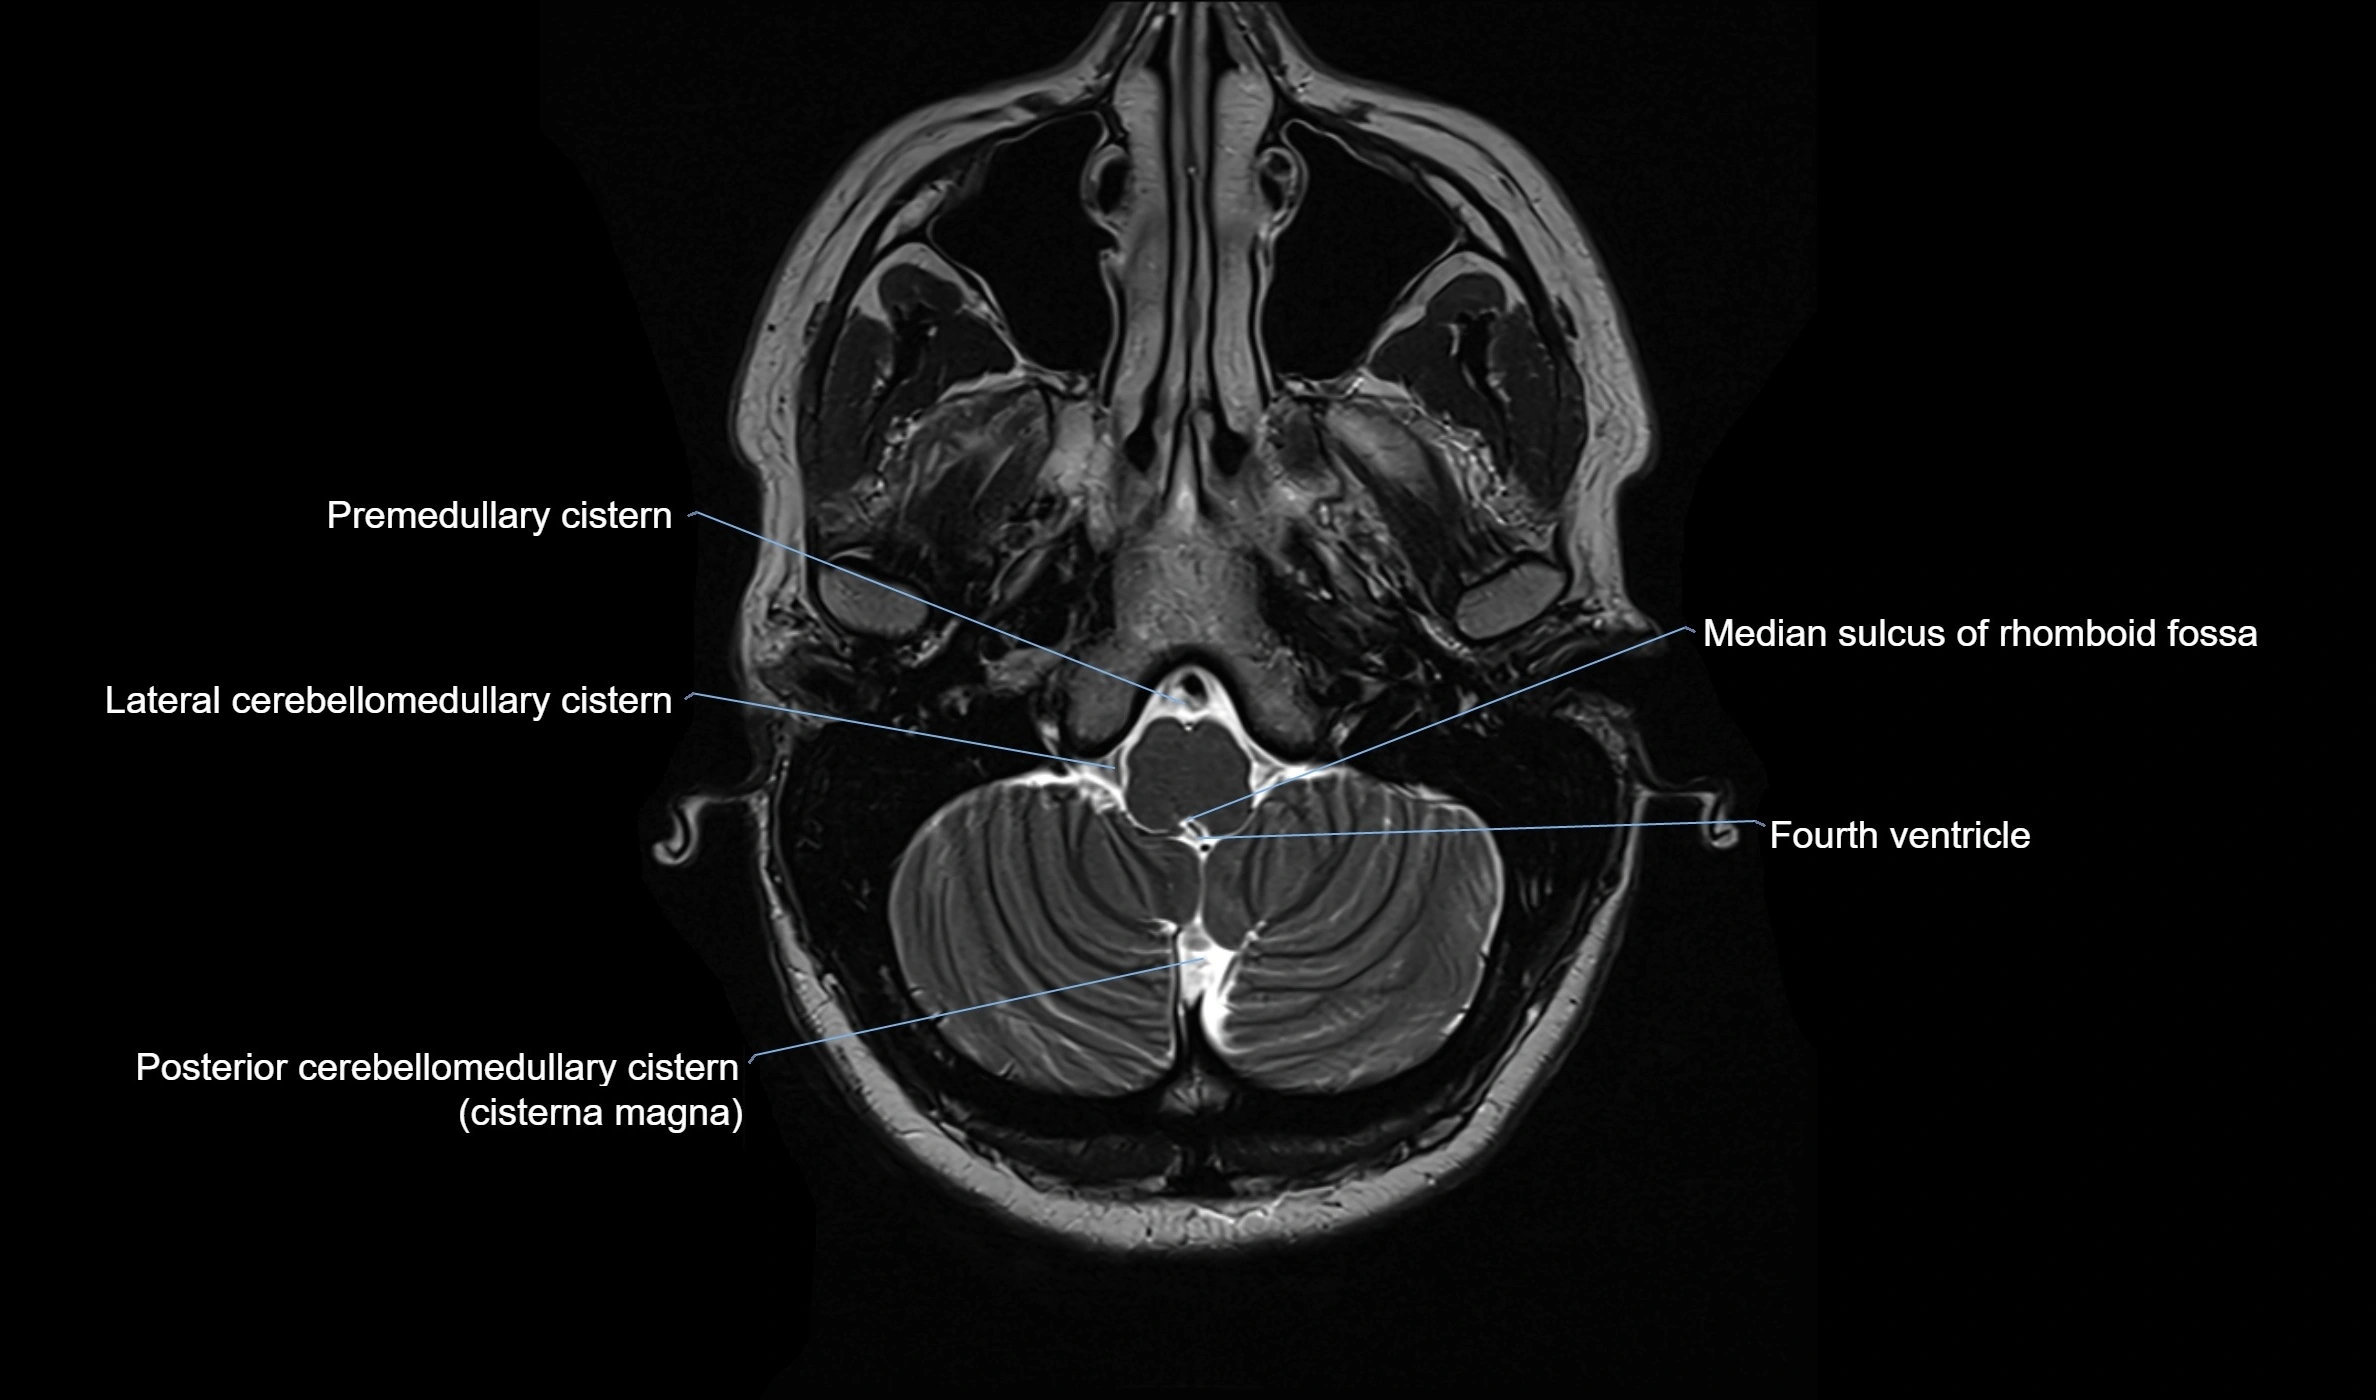

The ambient cistern is a paired, narrow, and elongated subarachnoid space located bilaterally along the lateral aspect of the midbrain. It serves as a conduit between the interpeduncular cistern anteriorly and the quadrigeminal cistern posteriorly. This cistern houses critical neurovascular structures, including parts of the posterior cerebral artery, superior cerebellar artery, trochlear nerve (cranial nerve IV), and the basal vein of Rosenthal. It plays an important role in the circulation of cerebrospinal fluid (CSF) and provides an anatomical corridor for various vessels and nerves passing around the midbrain.

MRI Appearance

• T2-weighted images:

• The cistern is hyperintense (bright) due to the high water content of CSF.

• Encapsulated vessels and nerves are seen as flow voids or hypointense lines within the bright background.